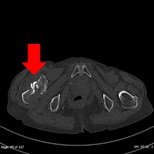

- 骨

| 骨折、その他骨異常の精査を目的とした撮影を行います。一般撮影では分かりにくい小さな骨折を観察することが可能です。また専用のワークステーションを用いて三次元的に骨折を把握することも可能です。 | ||

| 横断像 | MPR画像 | VR画像 |

| 右股関節転子下骨折 | ||